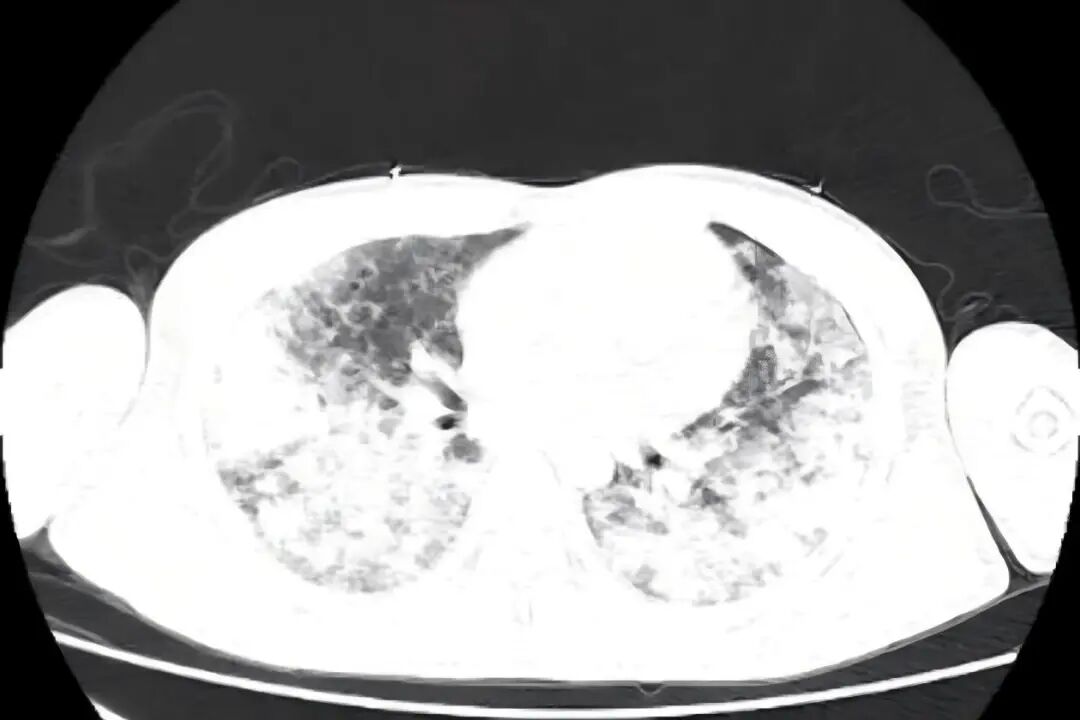

国庆假期期间,我院ICU成功救治一名罹患“罕见、危重、复杂”呼吸疾病的29岁患者。该患者因急性呼吸衰竭伴大咯血由外院紧急转入,入院时病情极为危重,胸部CT显示双肺弥漫性病灶,气管插管见大量血性液体,血氧饱和度一度降至50%以下。 入院时 CT提示双肺弥漫性病灶 近日复查 双肺渗出病灶明显吸收 入院时 肺部大量血性液体 住院期间 肺泡出血情况改善 接诊后,ICU团队迅速给予呼吸机支持、床旁支气管镜检查等救治措施,稳定患者生命体征。同时,医务部立即启动应急机制,组织呼吸与危重症医学科、肾脏风湿科、医学影像科、心血管内科、药学部等多学科专家会诊,国务院政府特殊津贴专家、呼吸与危重症医学科学科带头人廖江荣教授为患者进行床旁气管镜肺活检及支气管灌洗,诊断为弥漫性肺泡出血综合征(临床罕见、死亡率极高)合并急性呼吸窘迫综合征,为后续治疗提供了关键的循证依据。 ICU团队根据病情变化及时调整治疗措施,经过9天的精心治疗,患者生命体征保持平稳,肺泡出血情况逐步改善,肺部影像学表现明显好转,成功脱离了呼吸机支持,并转入普通病房继续治疗,现已好转出院。 专家提醒 弥漫性肺泡出血是以痰中带血、咯血、呼吸困难、进行性贫血和影像呈弥漫性肺泡浸润为特征的临床综合征。可由多种因素激发,基础疾病也多种多样,并且多数发病迅速,缺少特异性诊断方法,若不能早期诊断、及时治疗,则病死率很高。 若出现原因不明的急性呼吸困难、咳嗽、咯血等症状,特别是症状在短时间内迅速加重时,务必高度重视,应立即前往具备急救条件的医院就诊,争取早期诊断和治疗。 对于伴有自身免疫性疾病等相关基础疾病的患者,需定期随访,规范治疗,以预防严重并发症的发生。 贵州航天医院重症医学科专家简介 国务院政府特殊津贴专家 呼吸与危重症医学科 学科带头人 二级教授 硕士研究生导师 主任医师 学术任职: 亚洲冷冻治疗学会副主席 中国医药教育协会介入微创专业委员会呼吸分会副主任委员 中国防痨协会超声专业委员会副主任委员 中国抗癌协会肿瘤微创治疗专业委员会常务委员  中国防痨协会多学科诊疗专业委员会常务委员 中国医疗保健国际交流促进会结核病学分会常务委员 第一届中国人体健康科技促进会呼吸介入专业委员会常务委员 中国抗癌协会第一届肿瘤组织间植入治疗专业委员会常务委员 西部呼吸介入联盟副理事长 贵州省医学会呼吸病学分会第六届委员会副主任委员 贵州省中西医结合呼吸专业委员会副主任委员 贵州省医学会结核病分会常务委员 遵义市呼吸内科专业医疗质控中心主任委员 遵义市中西医结合学会理事长 专业擅长:  呼吸系统(肺)疑难病的诊断及危重病的抢救,呼吸系统(肺)感染性、疑难性疾病介入快速诊断(ROSE),尤其在肺癌、肺小结节早期诊断,肺癌微创综合靶向治疗,难治性、复治性、重症肺结核诊疗,硬质支气管下复杂性气道狭窄诊治,纤支镜介入治疗气道肿瘤、结核、气道狭窄(球囊扩张、支架植入、高频电刀、氩气刀、冷冻、灌洗、注药、微波消融),间质性肺疾病的诊疗上具有极高水平;带领团队勇于创新,在贵州省率先开展多项新技术、新疗法,如CT引导下及纤支镜下I125粒子植入及CT引导下微波、冷冻消融介入治疗肺癌等多项新技术,带动了贵州省肺部疾病的介入治疗水平提高。 刘东育 中共党员,重症医学科主任,主任医师 专业擅长:从事重症医学领域多年,擅长急危重症的各种抢救,有创呼吸机、无创呼吸机及CRRT的使用,对重症创伤及休克、急性重症胰腺炎、心脑血管疾病、各种急性中毒、多器官功能衰竭、重症肺炎及急性呼吸窘迫综合症等疾病的救治具有丰富的临床经验。 遵义市医学会重症医学分会第二届委员会常务委员,遵义市质量控制中心第一届重症医学质量控制中心委员会副主任,发表重症医学专业论文多篇,遵义市医学会第一届器官捐献与移植学分会常务委员。 赵洪伟 民建会员,重症医学科副主任,副主任医师 专业擅长:从事重症医学领域多年,擅长急危重症的各种抢救,有创呼吸机、CRRT的使用,对各种急性中毒、多器官功能衰竭、重症创伤及休克、心脑血管疾病、急性重症胰腺炎及急性呼吸窘迫综合症等疾病的救治具有丰富的临床经验。 贵州省重症医学委员会委员、遵义市重症医学会委员、遵义市医学会重症医学分会委员,贵州省第一批援沪医疗队队员,发表重症医学专业论文多篇。 王  磊 致公党党员,重症医学科副主任医师 专业擅长:从事重症医学多年,擅长急危重症的各种抢救,对急性重症胰腺炎、重症创伤及休克、急性呼吸窘迫综合症等疾病的救治、有创呼吸机的使用,CRRT对各种急性中毒、多器官功能衰竭、脓毒血症等疾病的救治具有丰富的临床经验。 贵州省重症医学委员会委员、遵义市重症医学分会委员、遵义市播州区方舱医院医疗队队员。 吴英武 中共党员,重症医学科副主任医师 专业擅长:擅长各种急危重症的抢救,对脓毒血症、重症创伤及休克、重症胰腺炎、急性呼吸窘迫综合症等疾病的救治及在重症超声对危重症治疗、抢救等方面具有丰富的临床经验。 贵州省第一批援鄂医疗队队员、贵州省重症医学委员会委员、遵义市医学会重症医学分会委员,发明专利3项、发表重症医学专业论文多篇。 贵州航天医院重症医学科简介 贵州航天医院重症医学科目前共有医护人员27人,其中副高级以上专家5人,开放床位16张,床单元配备医疗桥架和床旁监护系统,心电监护27台、动态血流监测仪23台、有创呼吸机19台、无创呼吸机5台、高流量呼吸机2台、转运呼吸机1台、血气分析仪1台、除颤仪1台、床旁透析机1台、纤支镜1台、无创血流动力学监测仪(USOM)1台、床旁B超机1台,降温毯1台、输液泵10台、微量注射泵74台、空气消毒机2台。 专科特色技术 心脏电转复及除颤术,气管插管术(经鼻气管插管术、经口气管插管术),气管切开术(经皮快速气管切开术、纤支镜引导下经皮快速气管切开术、超声定位纤支镜引导下经皮快速气管切开术),呼吸机的临床应用、心电、血压、脉搏、血氧饱和度监测技术、有创动态血压监测技术,有创动静脉置管术、锁骨下静脉穿刺技术、颈内静脉穿刺术、股静脉穿刺术、腋静脉穿刺置管术、血液净化临时血管通路的建立、鼻空肠置入术,跨肺压指导ARDS通气患者PEEP滴定应用,床旁超声测量视神经鞘直径评估颅内压,重症肺部超声评分在COPD患者中治疗效果应用,重症膈肌超声运动评估在机械通气患者撤机拔管中的应用,床旁超声测量下腔静脉呼吸变异指数在脓毒性休克机械通气患者容量反应性评估中应用价值。 诊疗范围 (一)急性、可逆、已经危及生命的脏器功能不全,经过严密监测和加强治疗短期内可能得到康复的患者。 (二)存在各种高危因素,具有潜在生命危险,经过严格监护和有效治疗可能减少死亡风险的患者。 (三)在慢性脏器功能不全的基础上,出现急性加重且已危及生命,经过严密监测和治疗可能恢复到原来状态的患者。 (四)其他适合在重症医学科进行严密监测和加强治疗的可逆性疾病患者 END